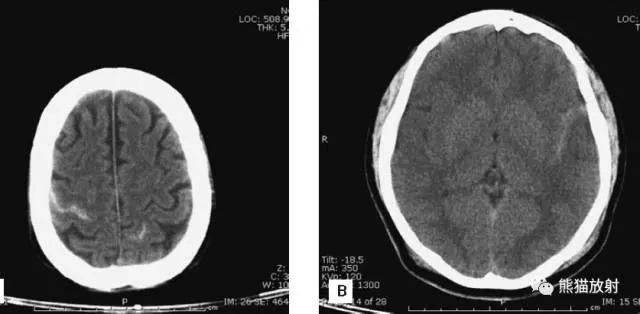

5、侧脑室体部层面

由额、颞、枕叶构成,两侧侧脑室体部之间为透明隔,外侧为尾状核和体部。侧脑室后角(枕角)可不对称,室内可见脉络丛钙化。中线处可见大脑纵裂池和大脑镰。

6、侧脑室上部层面内侧壁侧脑室体部被胼胝体分开,侧脑室体部的外方为顶叶,顶枕沟及中央沟将大脑为为额、顶、枕叶。